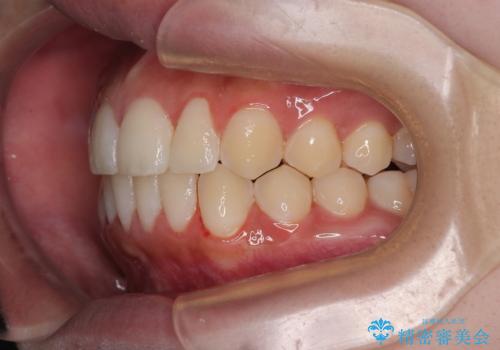

目立たないマウスピース矯正で下の前歯のデコボコをスッキリ解消!たった1年で整った歯並びに

- 今回は「下の前歯のデコボコを治したい」と来院された患者様の症例をご紹介します。

患者様は「目立たない装置で矯正したい」との希望があり、当院では透明なマウスピース型矯正装置(インビザライン)による治療を提案しました。

診察してみると、下の前歯が並ぶためのスペースが足りないことが、歯並びがデコボコしている原因でした。

この計画により、デコボコだった下の前歯はしっかりと並び、わずか1年で治療を終えることができました

見た目が気にならないマウスピース矯正だったこともあり、患者様にも大変ご満足いただけました。